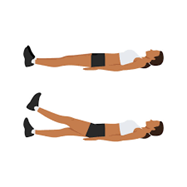

- بلند کردن مستقیم پا (تصویر شماره ۱۳) : این ورزش هم عضلات چهار سر ران را تقویت می کند و در تاندون ها و هم عضلات پشت ران شما کشش ایجاد می کند.

(تصویر شماره ۱۳)

پای راست خود را خم کرده و عضلات ران خود را سفت کنید. به آرامی و به صورت کنترل شده، پای راست خود را از زمین بلند کنید.

پای راست را تقریباً به اندازه ۴۵ درجه بلند کنید، یا تا وقتی زانوی راست شما با زانوی چپ شما یکسان شود.